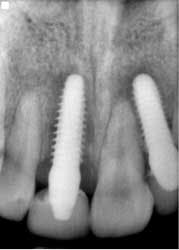

Fig. 3: Implant temporization No. 8 and No. 10 — 3.7 mm x 13 mm implant placed on No. 8.Patient returned one month later after returning from a cruise, complaining that her “implants felt loose.” She was very honest and admitted to not taking the antibiotics and not following any dietary restrictions while on vacation, because “they felt so strong.” Periapicals taken that day showed a catastrophic failure, with large areas of bone loss surrounding both implants (Fig. 4).

Implant sites were curetted well, then disinfected with Chloramine-T saturated gauze, followed by irrigation with 2% chlorhexidine and water. Bone grafting was not deemed necessary. Both implants No. 8 and No. 10 were replaced with TRX-OP 4.5 x 13 mm (Fig. 5). The patient was informed that because implants placed into previously failed sites have a lower success rate, absolute adherence to postoperative instructions was critical to any chance of success (4). Instructions were once again given to follow dietary restrictions and take the antibiotics as prescribed. The patient was seen six weeks postoperatively (Fig. 6) and set to have the final prosthesis inserted six months post-reimplantation.Fig. 5: No. 8 and No. 10 — implants replaced by 4.5 x 13 mm and retemporized.